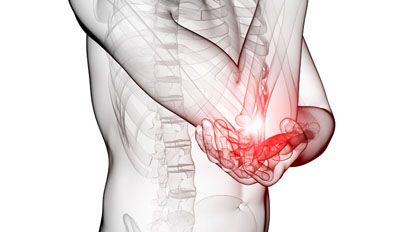

1. 后背疼痛

下背部疼痛(紧皱)常常与肾脏问题有关,这可能是肾结石的一种信号。这些疼痛常常还会伴有水肿等症状。另外,经常久坐不动的人也会出现后背疼痛的症状。